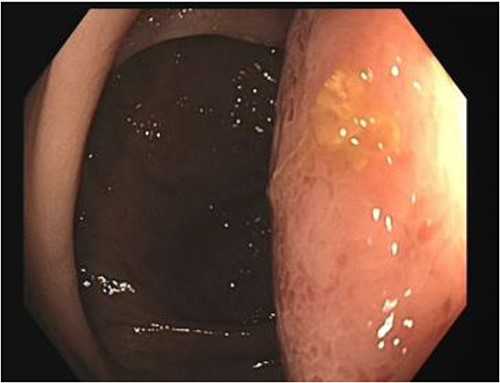

A number of differential diagnoses were considered including neoplastic and infectious pathologies such as latent TB, hydatid or amoebic cyst. A subsequent colonoscopy showed a submucosal semi-pedunculated lesion in the ascending colon measuring greater than 50 mm (Fig. 3). Biopsies were histologically nonspecific. As the patient was symptomatic of this lesion, and moreover as a malignant process could not be excluded, he proceeded with a surgical resection.

Histopathology macroscopically identified a 42-mm cystic caecal mass adjacent to the ileocaecal valve (Figs 4–5). Microscopic examination revealed a duplication cyst involving the ileal and colonic tissue comprised of a complete duplication of the colonic wall including mucosa, submucosa and muscularis propria, which was shared with the involved colon (Fig. 6). There was no mucosal connection to adjacent normal bowel. There was some ulceration with inflammatory changes in the overlying mucosa suggestive of prior cyst perforation and areas of attenuated villiform mucinous epithelium with features of low grade dysplasia (Figs 7-8). Special stains for organisms (Periodic Acid-Schiff (PAS), Fredericamycin A (FMA), Ziehl-Neelsen (ZN) and modified ZN) were negative. There were no granulomas, heterotopic mucosa or evidence of malignancy. Twenty-nine lymph nodes were identified with no evidence of malignancy.